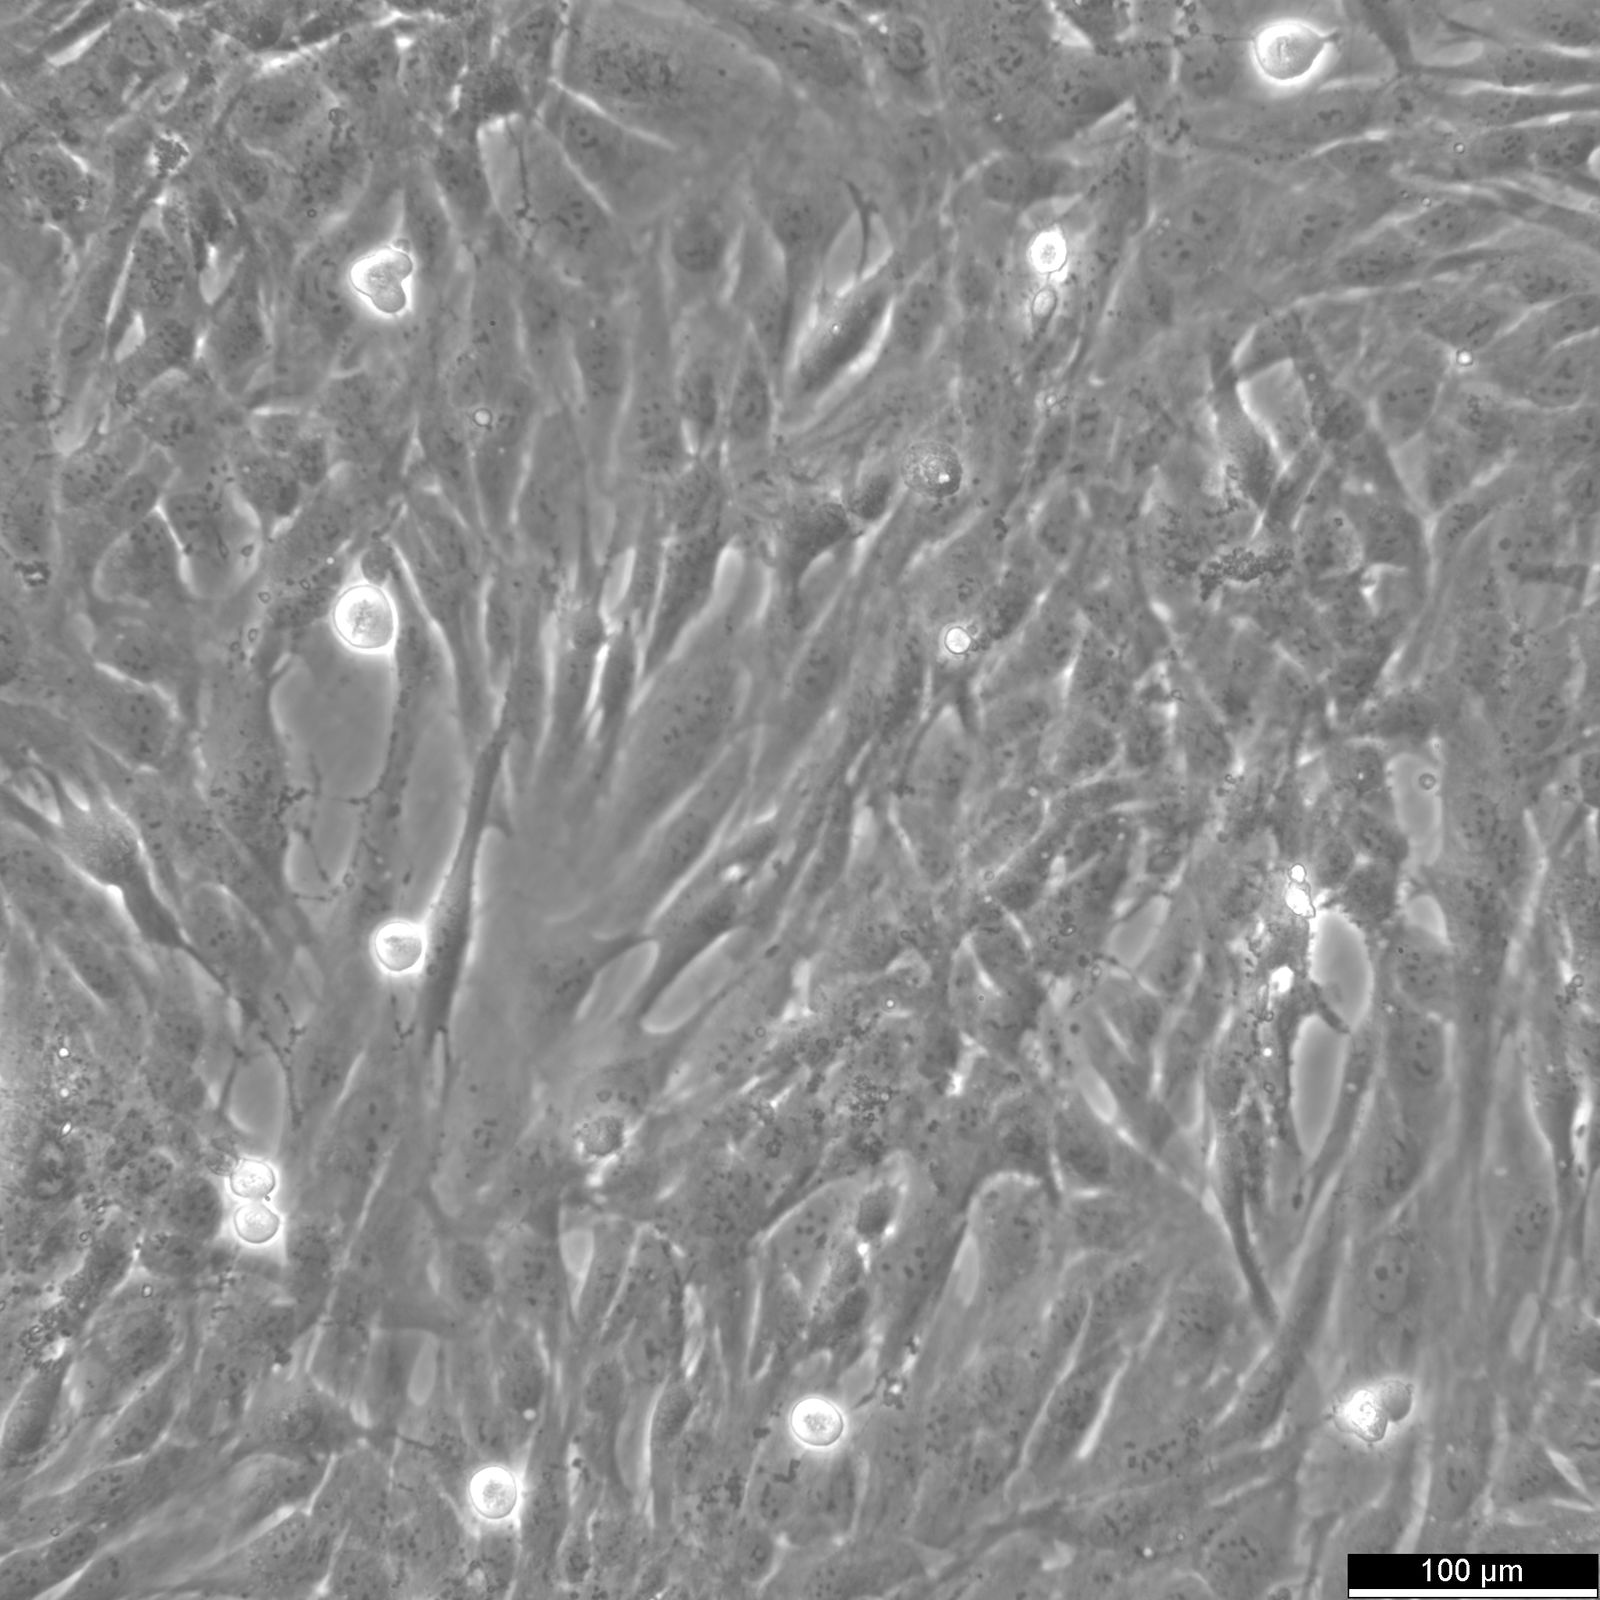

Categories: Hybrid cell lines Description: The AC16 cell line, derived from human ventricular cells fused with SV40-transformed, showcases characteristics typical of cardiomyocytes, including the expression of transcription factors such as GATA4, MYCD, NFATc4, and contractile proteins like alpha- and beta-myosin heavy chain. AC16 cells also express gap junction proteins connexin-43 and connexin-40, with functional gap junctions confirmed by dye-coupling studies, underscoring their utility in cardiomyocyte research. When the SV40 oncogene is silenced, AC16 transitions towards a more differentiated state, marked by the expression of BMP2, indicative of cardiac differentiation and developmental regulation. In general, scientists employ various techniques, including stem cell differentiation, animal models, molecular analysis, and biomarker discovery, to advance knowledge and potential therapies for heart-related conditions. The involvement of mitogen and senescence pathways, along with thymidine kinase induction, further elucidates the complex nature of human cardiomyocytes and their response to pathological conditions. The AC16 human cardiomyocyte cell line's ability to mimic the behavior of mature cardiomyocytes makes it a valuable model for cardiac research. It closely resembles the genetic makeup of primary cardiomyocytes, allowing for studies on cardiac development, pathology, and the implications of histone loss in vitro, however, the cardiomyocyte behavior and genetic complexity might not fully match that of primary or stem cell-derived cardiomyocytes. In the context of toxicology and cardiovascular disease research, AC16 cells serve as a vital tool for understanding cardiomyocyte development, inflammation, injury, regeneration, and toxicological effects. The unique properties of the AC16 human cardiomyocyte cell line, including its response to developmental cues and the ability to simulate the physiological conditions of human cardiomyocytes, make it an indispensable asset in the quest to unravel the mysteries of heart diseases and devise novel therapeutic interventions. Organism: Human Tissue: Heart, ventricle Synonyms: Human hybrid cardiomyocyte Ethnicity: Caucasian Morphology: Epithelial Cell Type: Cardiomyocyte Growth Properties: Adherent Citation: AC16 Cardiomyocyte Cell Line (Cytion catalog number 305215) Biosafety Level: 1 Ncbi_ Taxid: 9606.0 Cellosaurus Accession: CVCL_4U18 Viruses: Transformed by the SV40 large T-antigen Culture Medium: Culture medium:DMEM:Ham's F12 (1:1), w: 3.1 g/L Glucose, w: 2.5 mM L-Glutamine, w: 15 mM HEPES, w: 0.5 mM Sodium pyruvate, w: 1.2 g/L NaHCO3 (Cytion article number 820400a). Supplement the culture medium with 12.5% FBS and add 0.9 mM L-Glutamine to achieve a final concentration of 2.5 mM L-Glutamine. Differentiation medium: DMEM:Ham's F12 (1:1), w: 3.1 g/L Glucose, w: 2.5 mM L-Glutamine, w: 15 mM HEPES, w: 0.5 mM Sodium pyruvate, w: 1.2 g/L NaHCO3 (Cytion article number 820400a). To prepare the complete differentiation medium, add 1x ITS+ (Gibco, catalog number 41400045) and 2% Horse Serum (Gibco, catalog number 16050130). Dissociation Reagent: Accutase Subculturing: Remove the old medium from the adherent cells and wash them with PBS that lacks calcium and magnesium. For T25 flasks, use 3-5 ml of PBS, and for T75 flasks, use 5-10 ml. Then, cover the cells completely with Accutase, using 1-2 ml for T25 flasks and 2.5 ml for T75 flasks. Let the cells incubate at room temperature for 8-10 minutes to detach them. After incubation, gently mix the cells with 10 ml of medium to resuspend them, then centrifuge at 300xg for 3 minutes. Discard the supernatant, resuspend the cells in fresh medium, and transfer them into new flasks that already contain fresh medium. Freeze Medium: As a cryopreservation medium, use complete growth medium (including FBS) + 10% DMSO for adequate post-thaw viability, or CM-1 (Cytion catalog number 800100), which includes optimized osmoprotectants and metabolic stabilizers to enhance recovery and reduce cryo-induced stress. Thawing And Culturing Cells: Confirm that the vial remains deeply frozen upon delivery, as cells are shipped on dry ice to maintain optimal temperatures during transit. Upon receipt, either store the cryovial immediately at temperatures below -150°C to ensure the preservation of cellular integrity, or proceed to step 3 if immediate culturing is required. For immediate culturing, swiftly thaw the vial by immersing it in a 37°C water bath with clean water and an antimicrobial agent, agitating gently for 40-60 seconds until a small ice clump remains. Perform all subsequent steps under sterile conditions in a flow hood, disinfecting the cryovial with 70% ethanol before opening. Carefully open the disinfected vial and transfer the cell suspension into a 15 ml centrifuge tube containing 8 ml of room-temperature culture medium, mixing gently. Centrifuge the mixture at 300 x g for 3 minutes to separate the cells and carefully discard the supernatant containing residual freezing medium. Gently resuspend the cell pellet in 10 ml of fresh culture medium. For adherent cells, divide the suspension between two T25 culture flasks, for suspension cultures, transfer all the medium into one T25 flask to promote effective cell interaction and growth. Adhere to established subculture protocols for continued growth and maintenance of the cell line, ensuring reliable experimental outcomes. Sterility: Mycoplasma contamination is excluded using both PCR-based assays and luminescence-based mycoplasma detection methods. To ensure there is no bacterial, fungal, or yeast contamination, cell cultures are subjected to daily visual inspections. Safety Precautions: When planning to store a cryovial in liquid nitrogen for future thawing, it is mandatory to adhere to stringent safety measures. Appropriate protective gloves and clothing are essential, and the use of a face mask or safety goggles is required during the transfer of frozen samples to or from the liquid nitrogen tank. This is to mitigate the risk of injury from potential cryovial explosions upon removal, which can result in the projection of sharp fragments. Warranty: We stand by the promise of delivering products with high cell viability and robust culture performance. To achieve the best results, please make sure you follow the storage and culture instructions detailed in the product information sheet closely. Your adherence to these guidelines is key to success. Subject To Material Transfer Agreements: If you intend to use Cytion cell lines solely for internal research at a single research site, please complete and sign our Material Transfer Agreement (MTA) and submit it along with your order.For any commercial applications - including but not limited to fee-for-service work, quality control testing, product release, diagnostic use, or regulatory studies - please complete the Intended Use Form so we can prepare a suitable agreement tailored to your project.Please note: The MTA applies only to certain cell lines. If this notice and the MTA document appear on a product page, the agreement is applicable. For cell lines not covered by the MTA, no reference to the agreement will be shown. The MTA is not valid for customers in the Americas, China, or Taiwan. Please contact our U.S. entity to receive the appropriate agreement. Required Product 1: 820400a Required Product 3: 860015.0 Required Product 4: 830100.0